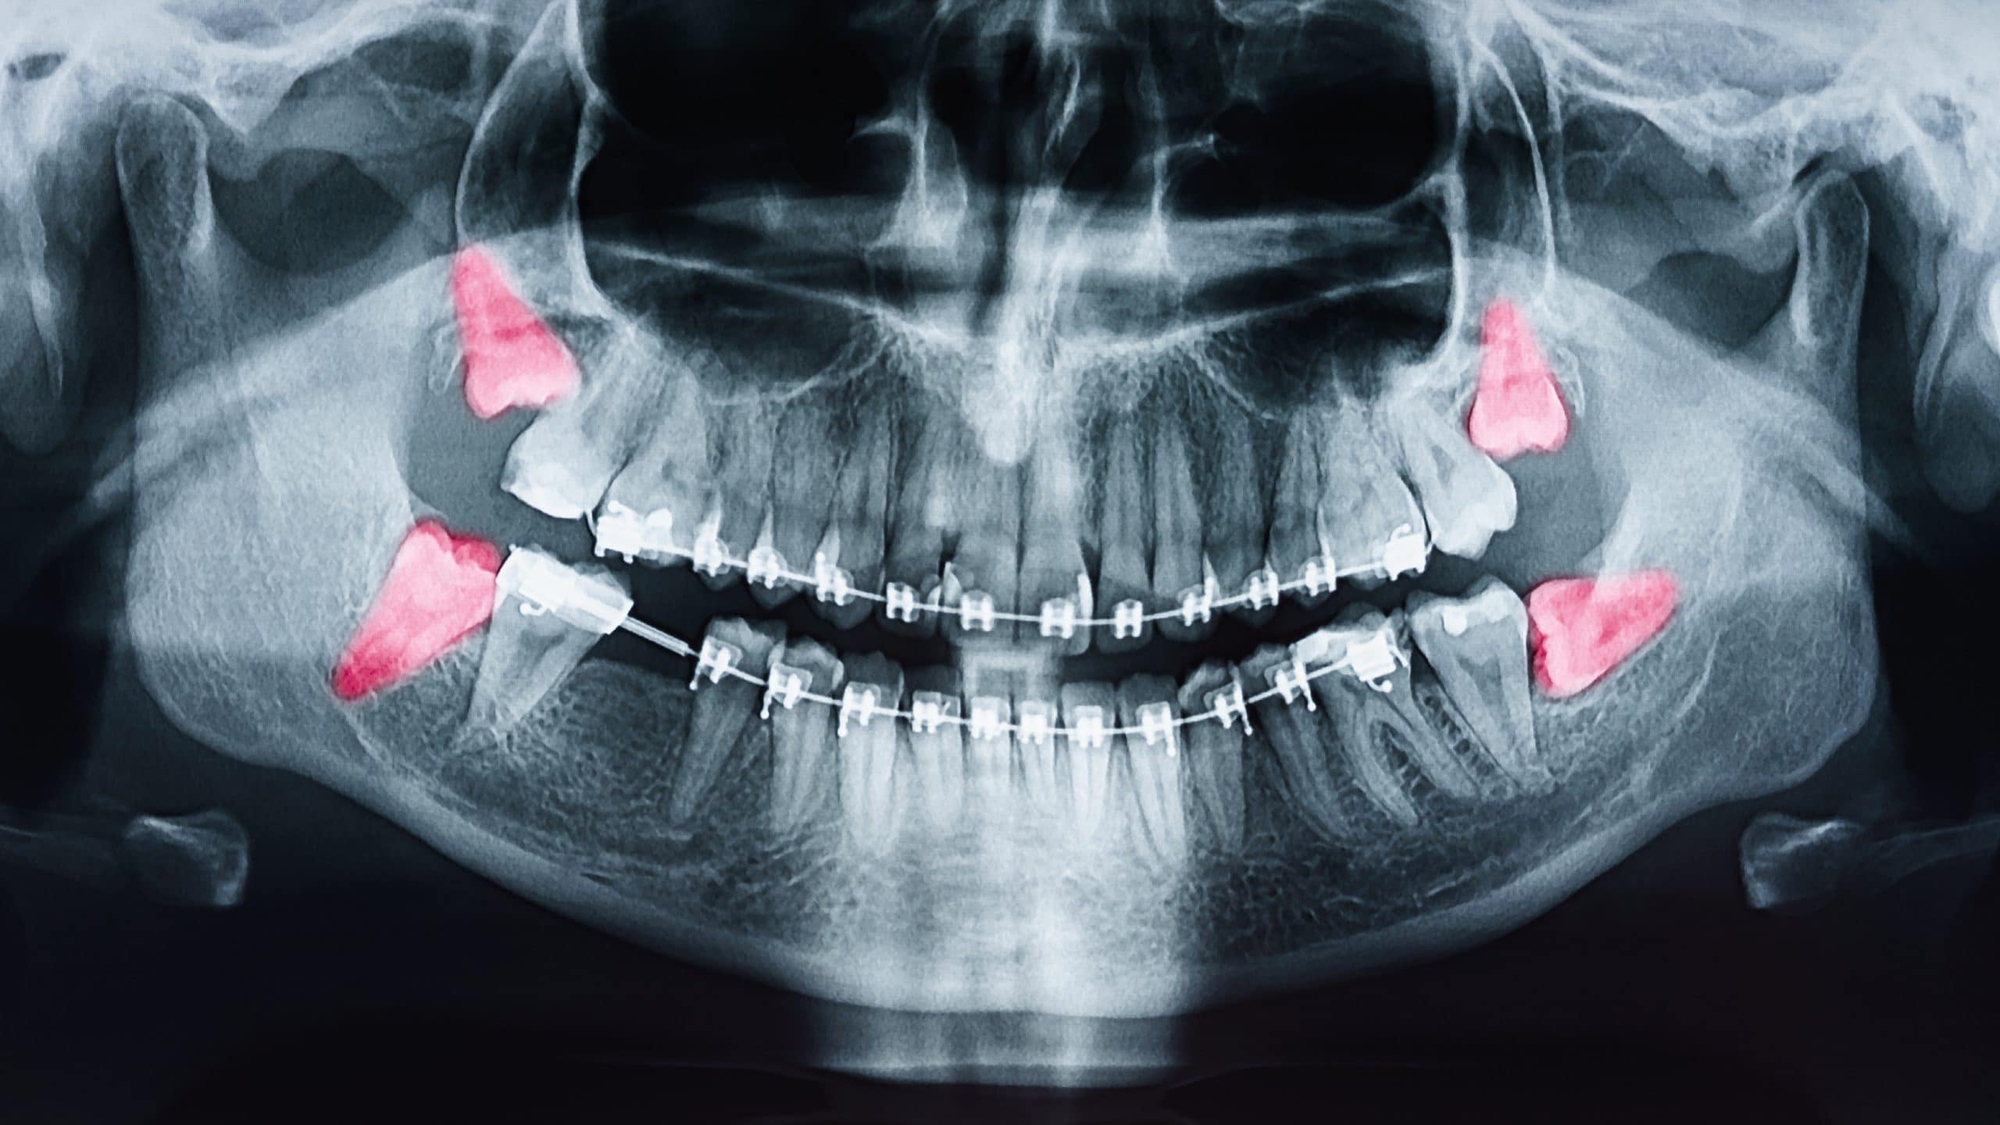

Vì mọc khi xương hàm đã cứng cáp, có niêm mạc, mô thì phủ dày bên trên nên khi răng khôn xuất hiện chúng sẽ thiếu không gian để phát triển. Cũng vì vậy mà những chiếc răng khôn thường mọc ngầm, bị lệch lạc hay đâm cả vào chiếc răng bên cạnh vì thiếu chỗ. Do đó quá trình mọc răng khôn khiến chúng ta bị đau đớn âm ỉ, khó chịu vô cùng. Những người bị nặng còn bị đau buốt, viêm nhiễm.

Trong thực tế, không phải người lớn nào cũng có răng khôn. Ước tính có khoảng 65% dân số sẽ mọc răng khôn và không phải ai cũng phải nhổ chúng đi. Chỉ các trường hợp bị răng khôn quấy nhiễu, ảnh hưởng đến hoạt động bình thường của răng miệng thì mới cần chỉ định đi nhổ răng. Hành trình nhổ răng khôn vẫn luôn là cơn ác mộng của rất nhiều người trưởng thành.